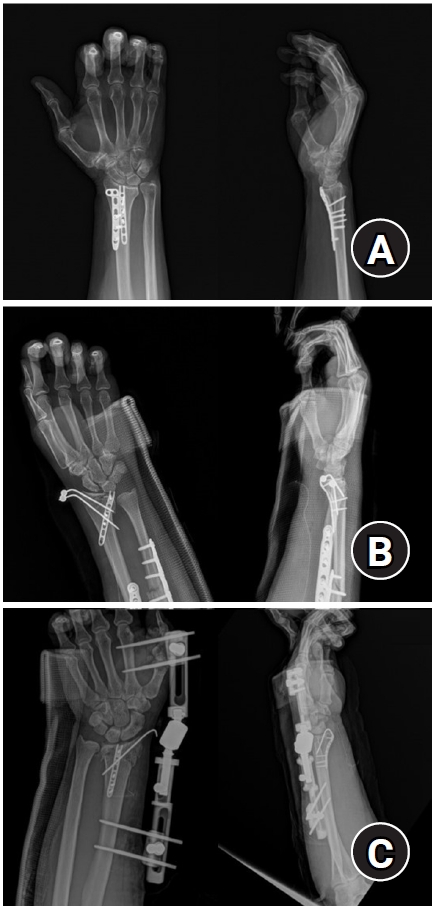

Fig. 4.

Postoperative radiographs (anteroposterior and lateral). (A) A 2.4 mm variable angle locking compression plate volar rim distal radius plate (Synthes) used for fixation in a distal radius fracture with a volar lunate facet fragment. (B) Acu-Loc volar distal radius plate (Acumed) used for fixation in a distal radius fracture with a volar lunate facet fragment.

Fig. 4. Postoperative radiographs (anteroposterior and lateral). (A) A 2.4 mm variable angle locking compression plate volar rim distal radius plate (Synthes) used for fixation in a distal radius fracture with a volar lunate facet fragment. (B) Acu-Loc volar distal radius plate (Acumed) used for fixation in a distal radius fracture with a volar lunate facet fragment.